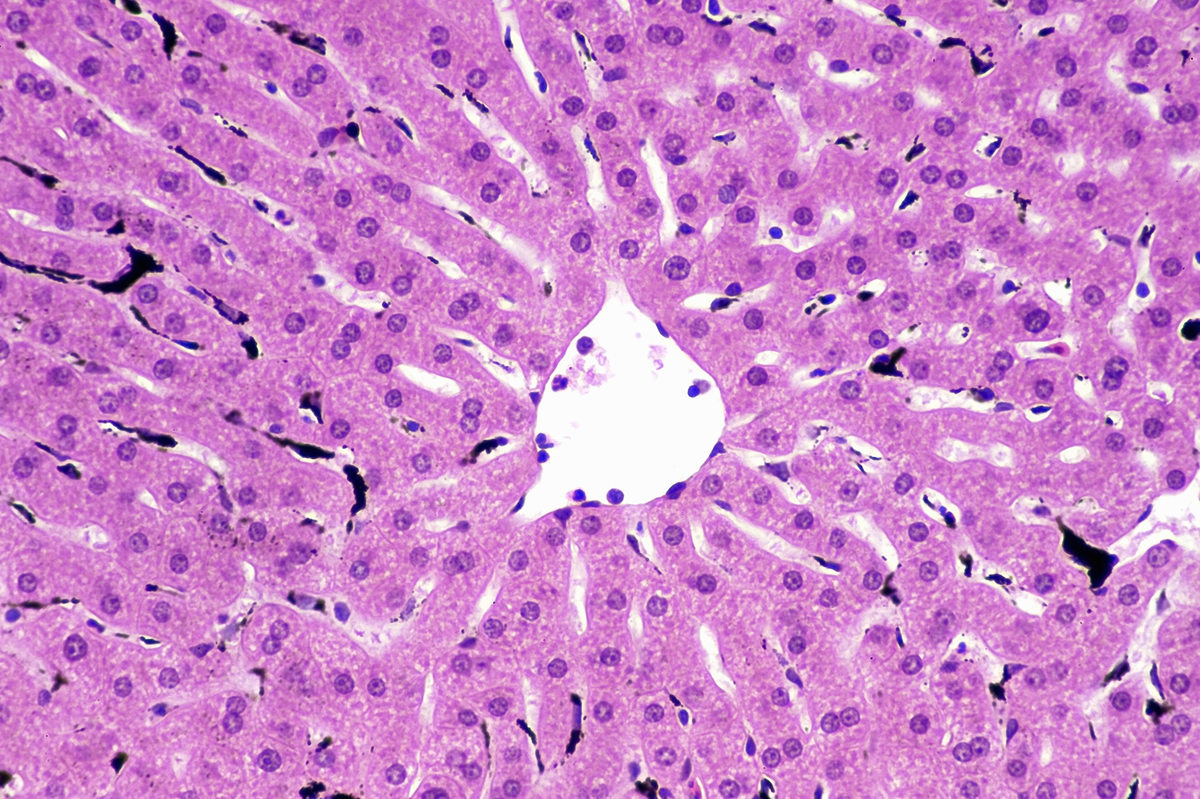

Клетки Купфера, фагоцитирующие частицы углерода. Иллюстрация: iecure.com

С помощью интравитальной микроскопии была выявлена популяция макрофагов, обитающих в печени, называемых клетками Купфера (КК), которые находятся в синусоидах и задерживают почти все бактерии, попадающие в кровоток. Этот жизненно важный контакт бактерий с поверхностью КК обеспечивает последующий фагоцитоз, который опосредуется каноническим комплементом и неидентифицированными рецепторами иммуноглобулинов. Специфическое удаление КК из синусоидов взрослых мышей приводит к неконтролируемому распространению бактерий и увеличению уровня летальности. Таким образом, внутрисосудистое расположение КК имеет решающее значение для предотвращения распространения бактерий из кровотока в другие органы.

Учитывая, что программа КК закладывается еще до рождения, КК должны быть способны проникать в синусоиды для очищения от бактерий в кровеносном русле. В предыдущем исследовании было описано, что КК ассоциированы с синусоидами, но имеют более округлую и менее разветвленную форму в печени плода, чем у взрослых. В данном исследовании мы изучили КК в неонатальной среде и выявили критическое паренхимальное и внутрисосудистое перемещение в первые несколько дней после рождения, что может объяснить значительное увеличение восприимчивости к инфекциям кровотока и значительную смертность новорожденных.